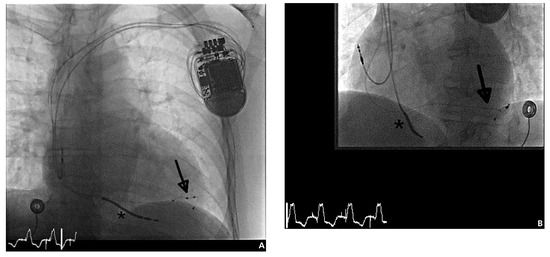

Abbildung 2. Durchleuchtung a.p. (A) und LAO 45° (B) nach Implantation des CRT-D mit der Option des Multisite bzw. MultiPoint™-Pacing (St. Jude Medical, Quadra Assura MP™). Die Einlage der 4-poligen LV-Elektrode (Pfeile) erfolgte konventionell transvenös über die Posterolateralvene des Koronarsinus. Die LV-Elektrode konnte hierbei distal im Zielgefäss in stabiler Position mit ausreichender Distanz zur rechtsventrikulären (RV-)Elektrode (Stern) platziert werden.